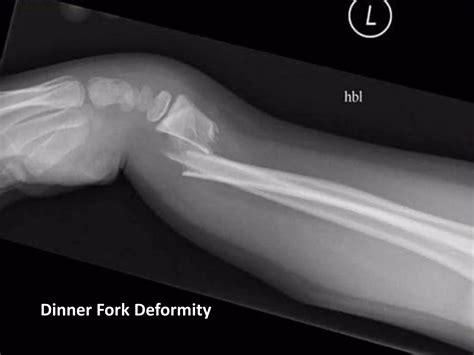

Dinner Fork Deformity

A sudden fall onto an outstretched hand is a common experience, but when that fall results in a visible, dramatic shift in the anatomy of the wrist, it often points to a specific and serious injury known as the Dinner Fork Deformity. This descriptive term is widely used in the medical community to characterize the classic presentation of a distal radius fracture, specifically a Colles' fracture. When the bone breaks and the fragments shift, the wrist takes on a shape remarkably similar to the handle and neck of an old-fashioned dinner fork. Recognizing this deformity is crucial because it serves as an immediate visual indicator that professional medical intervention is required without delay.

The Dinner Fork Deformity occurs primarily due to a fracture of the distal radius—the larger of the two bones in your forearm—at a point close to the wrist joint. When a person falls forward, the natural instinct is to extend the hand to break the fall. This puts immense, concentrated pressure on the wrist in a position called dorsiflexion (the hand bent backward). If the force of the impact exceeds the bone’s structural integrity, it snaps.

The “fork” appearance is created by the displacement of the distal fragment of the radius. Specifically, the broken end of the bone is pushed upward (dorsally) and tilted, causing a protrusion on the back of the wrist while the hand drops down relative to the forearm. This physical displacement is what creates the characteristic hump that mimics the curve of a dinner fork. This injury is particularly prevalent in two demographics: